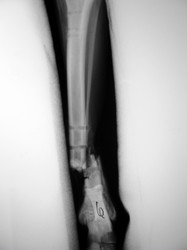

Fijación Externa

PRÁCTICAS CURSO DE FIJACIÓN EXTERNA PERFECCIONAMIENTO.

Híbrido.